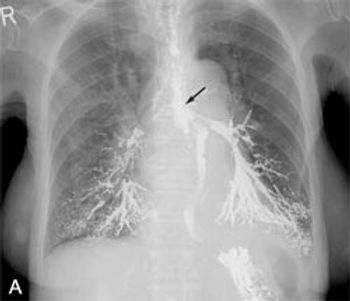

An 84-year-old woman presented with a 10-month history of dysphagia to solids and a 4-month history of dysphagia and coughing to liquids. She was severely dehydrated and cachectic; over the past 10 months, she had lost 16.2 kg (36 lb). Rhonchi and gurgling sounds were audible on auscultation of the chest.